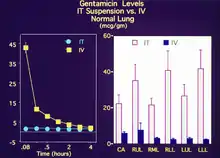

The second image shows experimental results comparing both plasma and tissue levels of gentamicin after an intratracheal (IT) and intravenous (IV) dose of 5 mg/kg in a newborn lamb during gas ventilation. Note that the plasma levels of the IV dose greatly exceed the levels of the IT dose over the 4 hour study period; whereas, the lung tissue levels of gentamicin when delivered by an intratracheal (IT) suspension, uniformly exceed the intravenous (IV) delivery approach after 4 hours. Thus, the IT approach allows more effective delivery of the drug to the target organ while maintaining a safer level systemically. Both images represent the in-vivo time course over 4 hours. Numerous studies have now demonstrated the effectiveness of PFC liquids as a delivery vehicle to the lungs.[35][36][37][38][34][39][33][40][30][41]